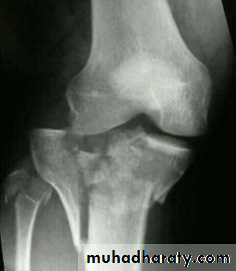

Tibial plateau fractures:Direct blow or fall from height may cause fracture of one tibial condyle or both.

Fracture lateral condyle is the commonest named as bumper fracture

caused by a force that abducts the tibia upon femur while the foot is fixed on ground.Patient usually is an adult, the knee joint is swollen, bruises, there is diffuse tenderness and doughy feel of haemarthrosis.

Imaging : X-ray

: anteroposterior, lateral & oblique views.

CT -Scan may used to detect amount of depression and comminuation.Tibial plateau fracture

Treatment:

Undisplaced fractures

treated conservatively:Haemarthrosis aspiration and compression bandaging,

above knee cast for one monthsfollowed by functional brace and physiotherapy.

For displaced fracturestreatment is by open reduction and internal fixation with

plate and screws as it is an intra articular fracture.fixation of tibial plateau fracture